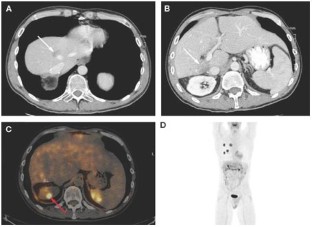

Background A 41-year-old male with a 4-year history of chronic hepatitis C presented with a 1-month history of abdominal pain, fatigue, weight loss, and night sweats.

Investigations Laboratory examinations, chest, abdomen, and pelvic CT scans, PET-CT scans, ultrasound-guided needle biopsies of liver lesions, bone-marrow biopsy, flow cytometry, and immunohistochemical staining for B-cell markers including CD20.

Diagnosis Chemoresistant diffuse large B-cell lymphoma, with gradual loss of CD20 antigen expression.

Management Embolization of hepatic tumors using yttrium-90 microspheres (Therasphere®, Theragenics Corporation, Buford, GA).